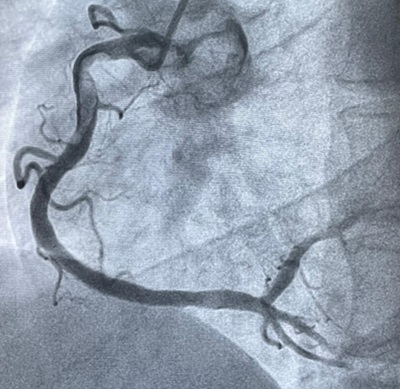

Case Description: A 45-year-old man presented to the emergency room with chest pain for the past 6 hours. He had history of multiple bee stings 14 hours ago. Review of systems was negative for rash, dizziness, palpitations or shortness of breath. He was a chronic smoker and alcoholic with no comorbidities and no history of allergies. He was conscious, oriented and his vitals were stable. ECG showed ST segment elevation in leads II, III and aVF (Figure 1). Echocardiogram showed mild left ventricular systolic dysfunction. Acute inferior wall MI and Kounis syndrome were suspected, and he was treated with routine ACS protocol, steroids and anti-histaminics. Coronary angiography showed mild, clinically insignificant atherosclerotic changes in the proximal right coronary artery (Figure 2), but absence of thrombus occluding the vessel. Patient was admitted in the cardiac intensive care unit and recovered well.